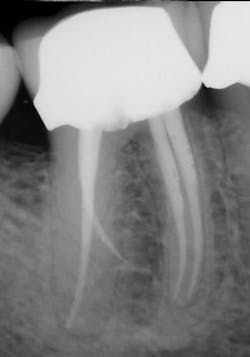

Figure 3: Radiograph showing master gutta-percha point fit to length.

I then use the Tango finishing instrument (double blue band on the latch head) in the same manner as described above. Always use the instrument wet. If you cannot achieve length, repeat the use of the Tango shaping instrument or use a 30/.04 SafeSider instrument to go to measurement. Confirm the Tango finishing instrument reaches the apical measurement. Move the instrument continuously against the canal walls until there is no resistance. I then fit the Tango-Endo gutta-percha point (figure 3). Figures 4 and 5 demonstrate the pre- and postop clinical radiograph.

Figures 4 and 5: Clinical pre- and postoperative radiographs using the Tango techniques described.